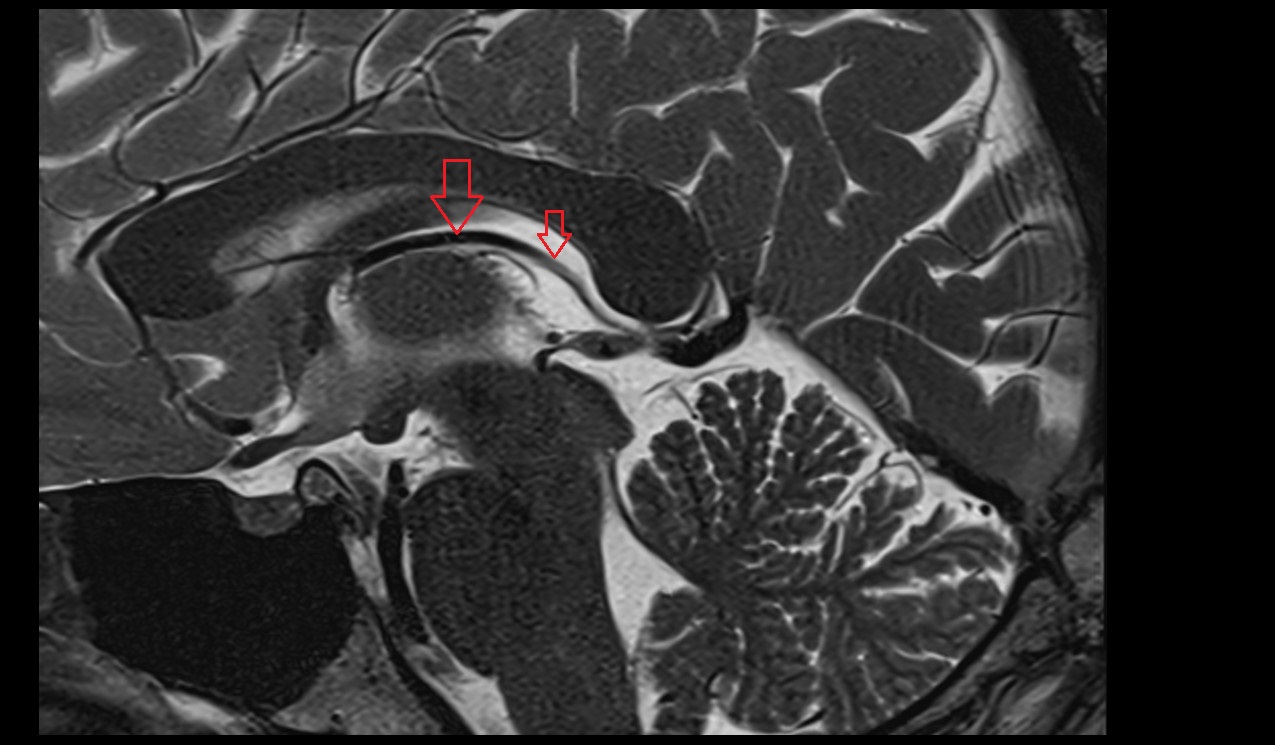

- Choroid fissure